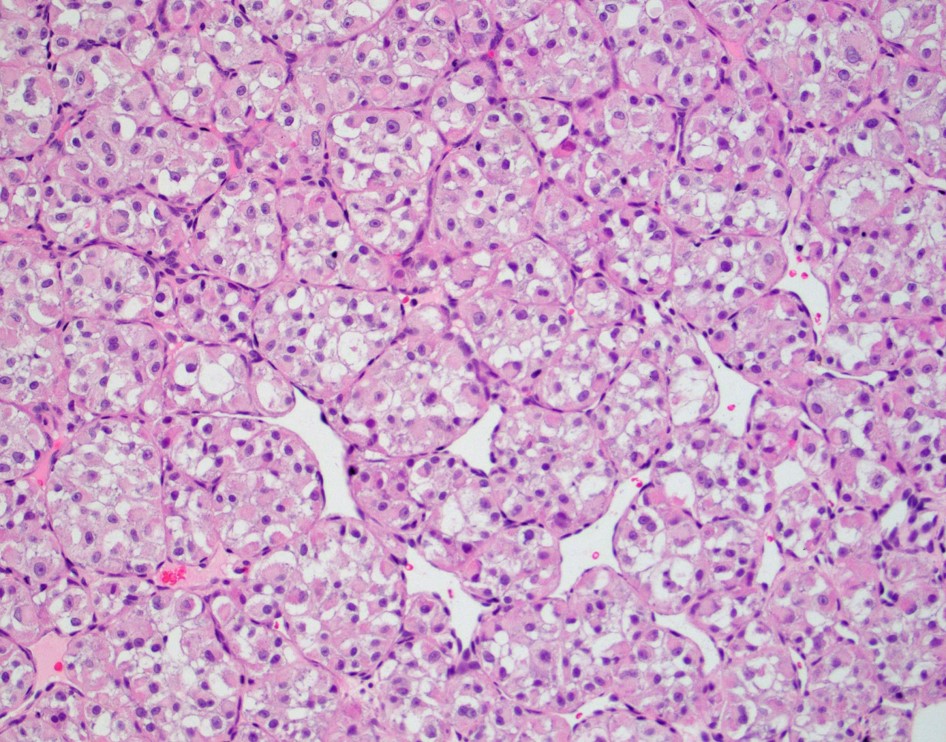

| The answer is “D”, Alveolar soft part sarcoma. Alveolar soft part sarcoma (ASPS) is a rare malignant neoplasm typically of infants, children and young adults containing a der(17)t(x;17)(p11.2;q25) translocation resulting in the fusion of the ASPSCR1 and TFE3 genes. Most common location is lower extremity but head and neck sites (tongue most common) are also affected. Histologically, ASPS shows a prominent lobular architecture formed by nests and lobules of tumor cells with fibrous septa and peripheral vascular channels. Nests of large polygonal cells with granular eosinophilic cytoplasm and nuclei containing prominent nucleoli are separated by sinusoidal vascular channels resulting in a pseudoalveolar pattern. Some cases can show sheet like growth. Intracytoplasmic rod shaped crystals are noted that are more easily seen with a PAS-D stain. Typical cases show cytological uniformity, but scattered pleomorphic cells can be seen. Mitotic rate is low and necrosis is uncommon. Immunohistochemically, there is nuclear TFE3 expression, and desmin is variably expressed. Myogenin, MyoD1, keratin, S100, HMB45 and S100 are negative. Treatment is surgical excision. Late recurrence and metastasis are common. Reference: Diagnostic Pathology. Soft Tissue Tumors. 2nd ed. Lindberg. Elsevier. |